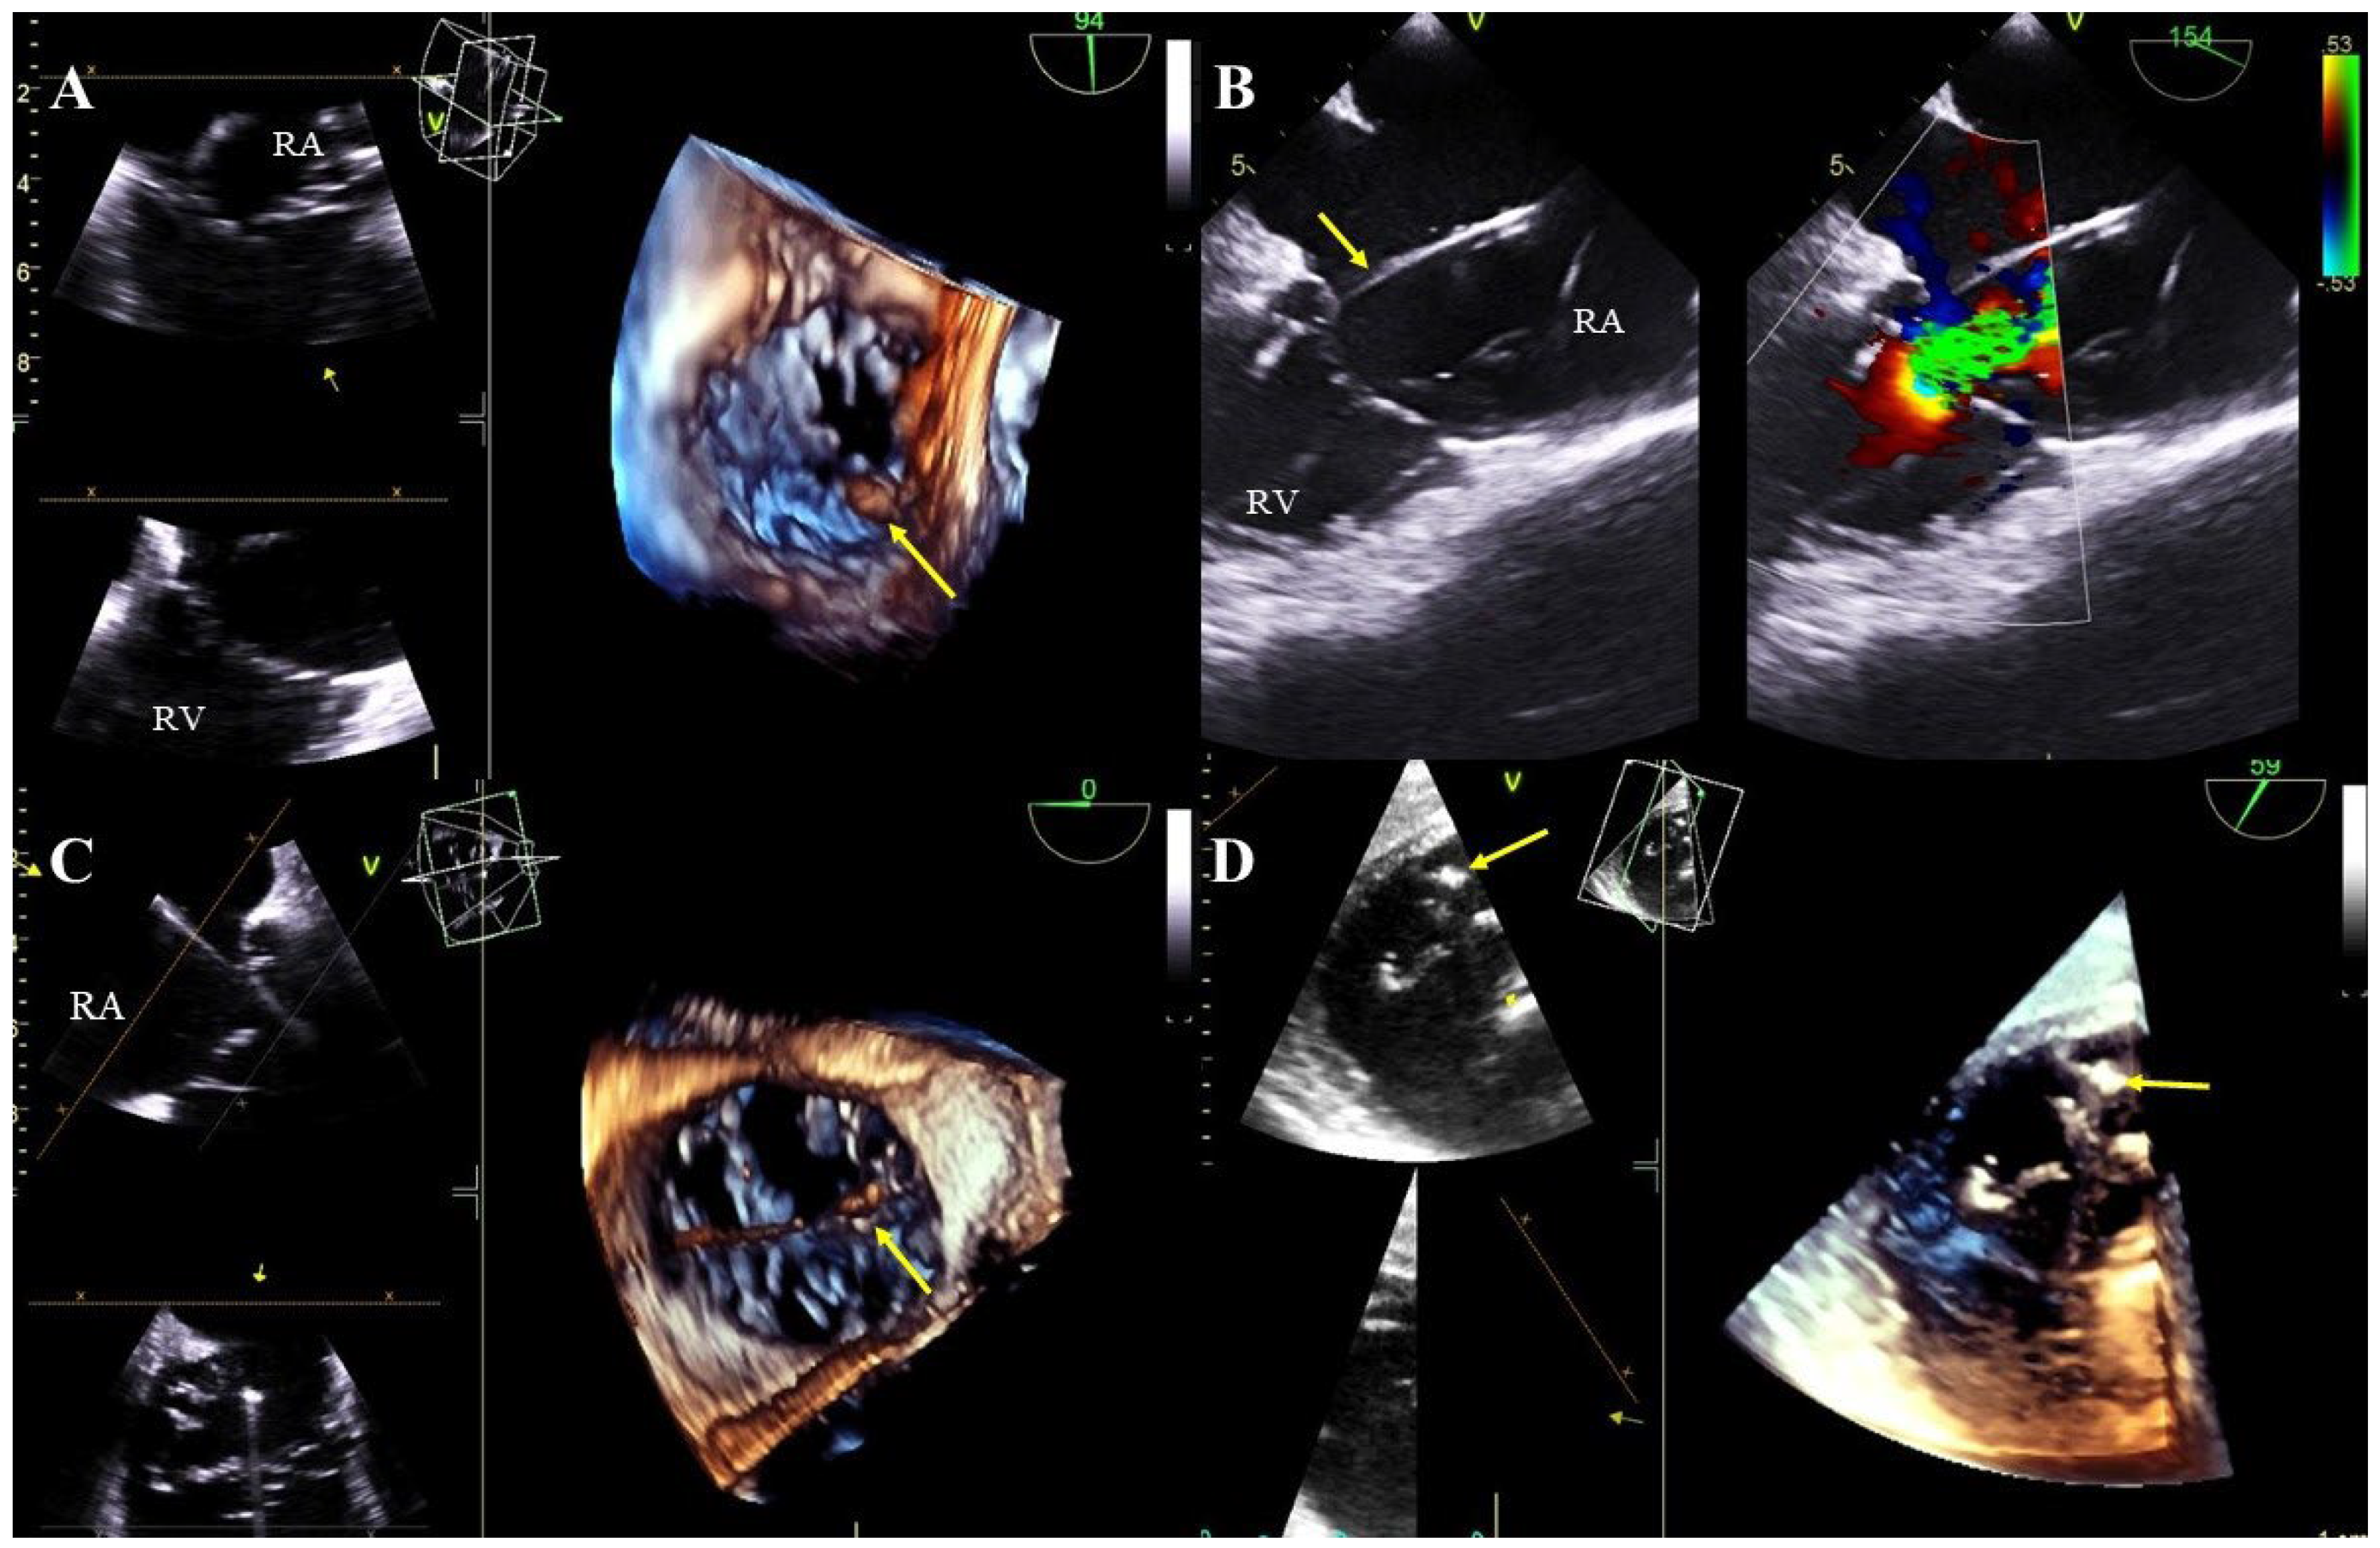

Lead thickening: segmental thickening and hyperechogenicity caused by the presence of scar tissue. Additionally, uneven outlines of the thickened lead segment with small mobile structures and with a consistent clinical picture may suggest an inflammatory process (Figure 3A–E, Movie S5).

Lead adhesion to surrounding structures: due to the presence of fibrous encapsulation, the lead adheres to the anatomical structures of the heart or the vein wall (Figure 3B–D, Movie S6). A characteristic feature is the joint movement of the bound elements. The term also includes lead-on-lead adhesions (two or three leads) that move together (Figure 3A,E, Movie S5). Attached masses binding the lead to the surrounding structures (vein wall or heart structures) are remnants of a previous asymptomatic inflammatory response to the presence of the lead in the heart. Over time, they may calcify or mineralize, crystallize or even ossify.

Lead-dependent tricuspid valve dysfunction (LDTVD): new valve regurgitation caused by the lead. The most common mechanism is impingement of the valve, adhesion of the lead to the leaflet or its perforation during implantation (Figure 4A–D, Movie S7).

Figure 3. TEE (2D, 3D) showing scar tissue around the leads. Segmental thickening of the leads and lead-on-lead adhesions in the right atrium (red arrow) (A). Pathological attachment of the two leads to the interatrial septum and to the atrial wall near the atrial appendage (red arrows). The narrowing of the vena cava at entry into the atrium is caused by the thickened leads and pathological scar tissue (Doppler color) (B). Thickened ventricular lead (yellow line) pathologically attaches to the endocardium of the interventricular septum in the right ventricle (C). The image from the right ventricle depicts a pathological adhesion (red arrows) of the lead to the edge of the tricuspid valve leaflet (D). Binding and intersection of thickened leads in the atrium (red arrow) (E).

Figure 4. Tricuspid valve dysfunction caused by the presence of the electrode (TEE 2D, 3D). The lead (yellow arrow) in the tricuspid valve supports the septal leaflet and hinders proper coaptation of the leaflets (TEE 3D) (A,C). Severe tricuspid valve regurgitation resulting from the septal leaflet being pathologically supported by the lead (yellow arrow), (2D, color Doppler image from panel A) (B). The posterior leaflet of the tricuspid valve is perforated by the lead (yellow arrow) (D).